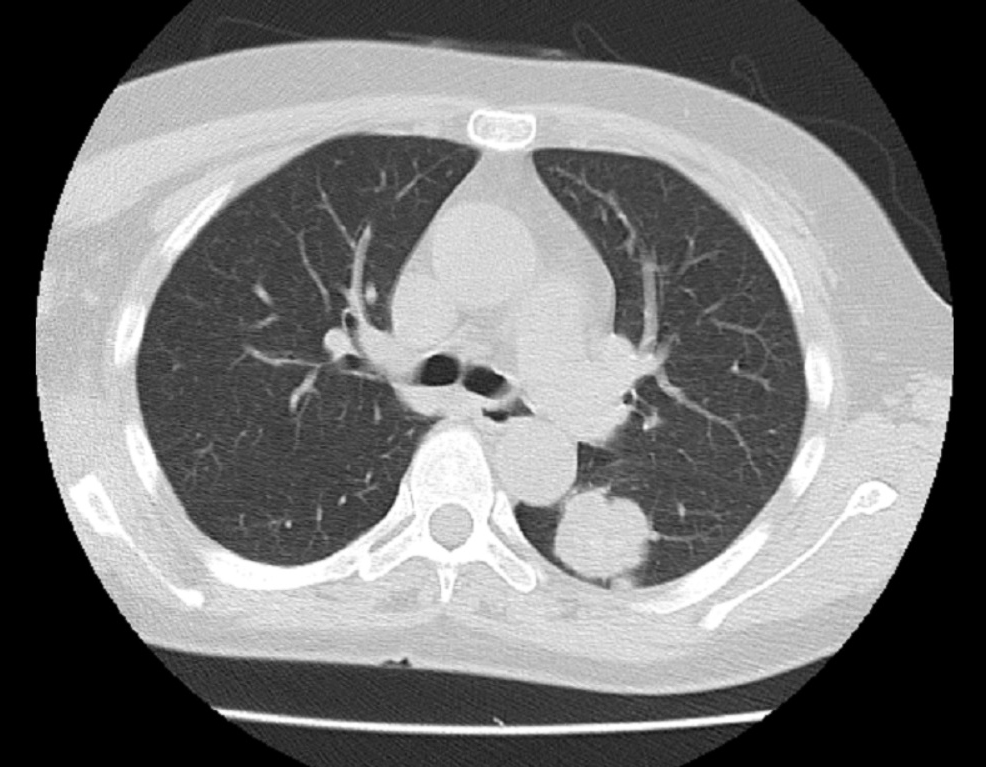

- 大腸がんの肺転移